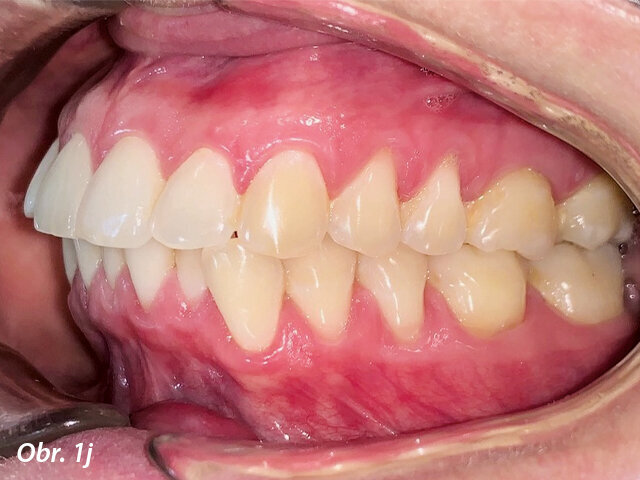

Po dalších devíti týdnech byla terapie dokončena. Bylo dosaženo dobrého vyrovnání zubů a korekce posunu střední čáry. Laterálně otevřený skus v oblasti molárů se spontánně uzavřel během měsíce po nasazení frontálních fixních retainerů.